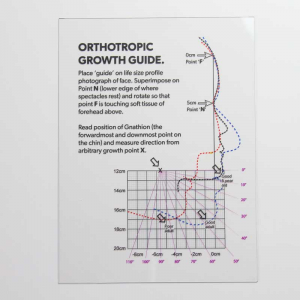

This kinda reminds me of the mew indicator line, indicator cheek line and what'd he go about evaluating SN line, FN plane and Cranial base angles

This kinda reminds me of the mew indicator line, indicator cheek line and what'd he go about evaluating SN line, FN plane and Cranial base angles

View attachment 4063432View attachment 4063433View attachment 4063434View attachment 4063436View attachment 4063438View attachment 4063439View attachment 4063440